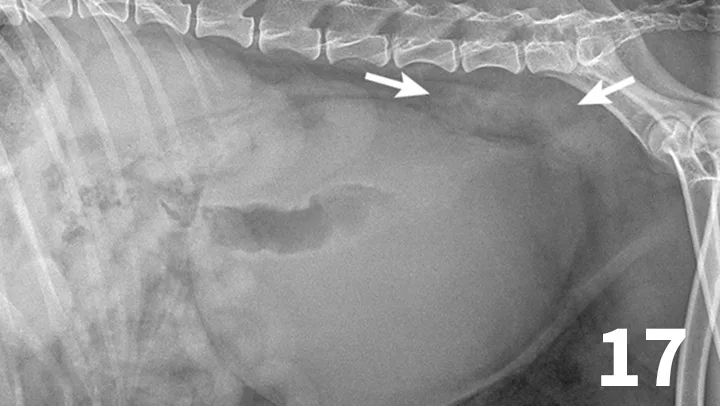

Survey radiographs of the urinary bladder are helpful for evaluation of size and location and for detection of radiopaque calculi. Urinary bladder distention is readily detected (Figure 17). Radiographs are of limited value in evaluating mural disease because the bladder wall cannot be differentiated from the fluid contained within the bladder. Bladder wall thickening (eg, bacterial inflammation, polypoid cystitis, neoplasia) is best evaluated by ultrasonography or double-contrast cystography (Figure 18). It should be noted that the degree of bladder filling can affect bladder wall thickness. For example, a small, mildly distended bladder may appear to have a thickened bladder wall on ultrasound compared with a moderately or severely distended bladder (Figure 19). This potential disadvantage can often be overcome by reevaluating the bladder several hours after preventing voiding.

This dog had a severely distended urinary bladder on evaluation of lateral abdominal radiographs. Ill-defined, soft tissue opacity was present in the region of the medial iliac lymph nodes (arrows). The dog had urethral neoplasia, which was the cause of the urinary outflow obstruction and lymph node enlargement.